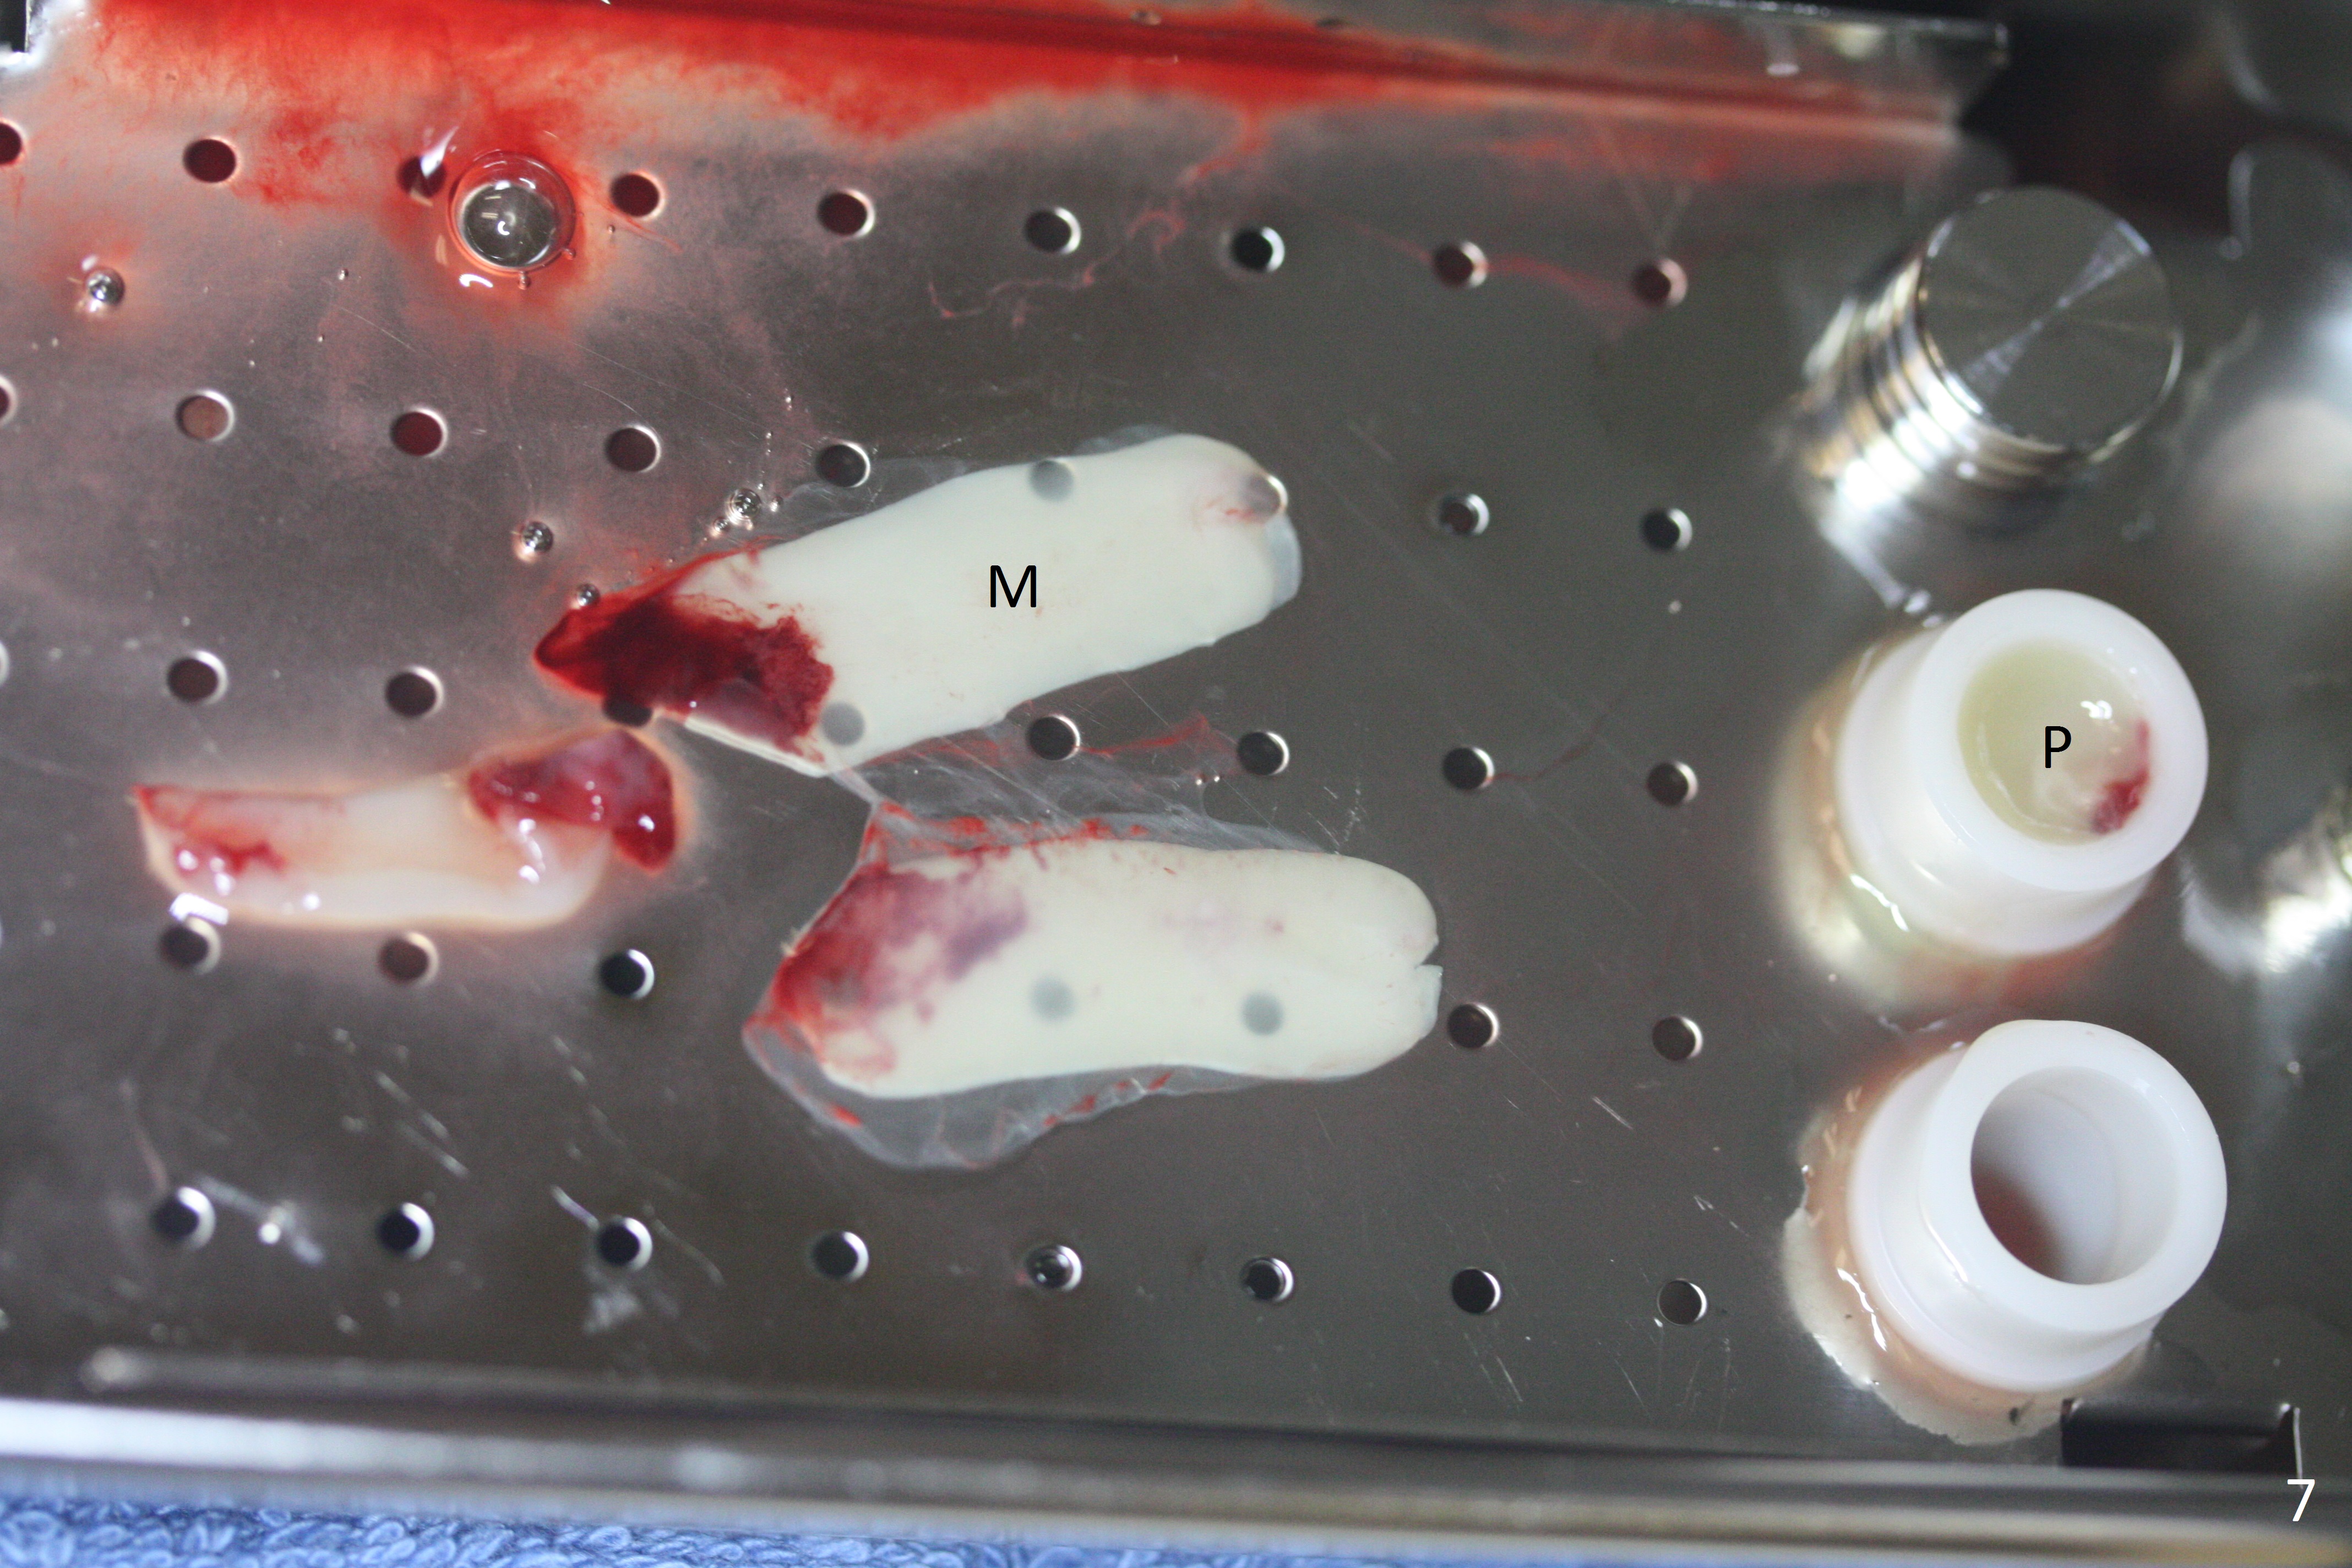

At #31, the implant has to be placed low because of low buccal bone (Fig.8 B (vs. much higher lingual (L) one) in spite of 2 mm implant being coronal to the distal bone (Fig.3 ^). The margin of the abutment with 6 mm cuff appears apical to the distal crest (Fig.3 *). Bone graft is placed around the exposed implant threads (Fig.6 *) after placement of Osteogen plug between the implants (P). After placing PRF membrane (Fig.7 M) and plug (P) over the bone graft, Cytoplast (Fig.6,8 C: non-resorbable membrane) is used to assist wound closure. Finally periodontal dressing is applied for further wound protection (Fig.9).